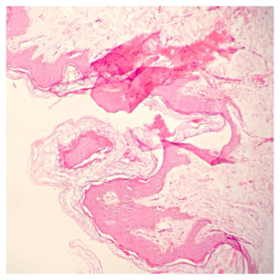

Láminas de Histología

Laboratorio de histología, Bibliografía Ross Pawlina 5ta Edición.